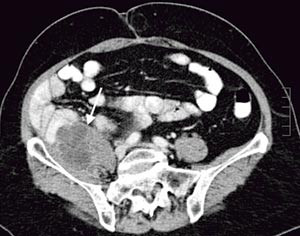

Pasienten. En tidligere frisk kvinne ble som 68-åring operert for cancer coeci med perforasjon. Det forelå en perikolisk abscess, og det ble gjort høyresidig hemikolektomi med reseksjon av fremre bukvegg. Inngrepet ble ansett som radikalt. I operasjonspreparatet fant man spredning til regionale lymfeknuter (Dukes C), og hun fikk derfor adjuvant kjemoterapi med 5-fluorouracil/leukovorin i seks måneder. Ett år senere utviklet hun sterke smerter i høyre flanke med utstråling til høyre lår, og ved CT ble det påvist en 12 cm stor tumor som infiltrerte m. iliopsoas dexter, oppfattet som et lokoregionalt residiv (fig 1). Det var ingen fjernmetastaser. Residivet ble resecert i muskulatur ved laparotomi, men tumorvev måtte etterlates omkring iliacakarene. Svulsten omsluttet n. femoralis, som måtte deles. Tumorsengen ble markert med metallklyper, og en brystprotese i silikon ble lagt på reseksjonsflaten for å skyve tynntarmen vekk fra det påtenkte strålefeltet (fig 2). Postoperativ CT viste likevel en interponert tarmslynge mellom protesen og fremre bukvegg (fig 3). Seks uker etter inngrepet ble det påbegynt radiokjemoterapi med 2 Gy x 25 som to motgående skråfelt og strålesensibiliserende 5-fluorouracil/leukovorin (fig 3). Under bestrålingen utviklet kvinnen høyresidig bekkenvenetrombose, og hun fikk antikoagulasjonsbehandling. Radioterapien var ledsaget av periodevise buksmerter, men uten diaré eller andre tegn til akutt stråleenteritt. Åtte uker etter endt bestråling ble hun igjen laparotomert. Den nevnte tarmslyngen frembød da ganske uttalte stråleskader. Protesen lot seg fjerne, i hovedsak ved stump disseksjon (fig 4). Pasienten ble likevel påført en ureterskade, som kunne repareres umiddelbart. Det var ingen gjenværende tumor, verken makro- eller mikroskopisk.

Operasjonsindikasjonen for vår pasient var smerter, og siktemålet var radikal fjerning av residivet, med tanke på både optimal palliasjon og mulig helbredelse. Da vi måtte etterlate svulstvev omkring iliacakarene, var det klart at håpet om kurasjon var betydelig redusert. Postoperativ bestråling ville likevel kunne utsette tiden til residiv, og det ble derfor gitt 50 Gy som to motgående skråfelt. Denne dosen kan synes lav – for å sanere makroskopisk tumorvev anses vanligvis doser under 60 Gy som utilstrekkelige, men med tarm i strålefeltet ble en så høy dose vurdert som risikabel. Et alternativ ville vært å gi tilleggsdoser konsentrert mot det etterlatte svulstvevet («boost»), men markeringen måtte da vært bedre enn tilfellet var. Intensitetsmodulert radioterapi (IMRT) vil snart være et tilbud ved norske stråleenheter. Ved slik behandling vil man i større grad enn ved tradisjonell doseplanlegging bli i stand til å begrense den høye bestrålingen til det tilsiktede målvolumet. Men behandlingen er ressurskrevende, og om pasienter av vår kategori vil kunne bli prioritert, gjenstår å se.

Implantasjon av brystproteser for å deplassere tynntarm har tidligere vært anvendt før bekkenbestråling (13, 14); ved abdominal bestråling er det kun rapportert brukt enkelte ganger (15). Mens migrasjon av protesen ikke utgjør noen stor risiko i bekkenet, er faren for dette større i abdomen. Av frykt for silikonlekkasje unnlot vi å fiksere protesen med suturer, og det viste seg at postoperative adheranser stabiliserte den uten forlenget sengeleie. En sikrere løsning kan være å pakke protesen inn i et resorberbart nett, som så sutureres til nabostrukturer (14). Det anbefales postoperativ kontrastundersøkelse for å kontrollere at tarm ikke interponeres i strålefeltet mellom protesen og tumorsengen eller i strålefeltet mellom protesen og bekken- eller bukveggen (13) – (15). Dette skjedde hos vår pasient, og, som vi kunne konstatere ved relaparotomien, var et tarmsegment blitt stråleskadet. Det er beskrevet flere teknikker for å forhindre dette, både transposisjon av omentum majus og innsying av resorberbare nett (13) – (15). Enkelte forfattere anbefaler saltvannsproteser i stedet for silikonproteser (14, 15). Fra et strålefysisk synspunkt er saltvannsproteser kanskje bedre egnet (16). Viktigere er det nok at en slik protese kan fylles i varierende grad slik at størrelsen kan tilpasses, og sist, men ikke minst, at en saltvannsprotese ikke nødvendigvis må fjernes – den kan aspireres perkutant etter endt strålebehandling slik at relaparotomi unngås (14). Fra mammakirurgien er det kjent at implanterte proteser kan være vanskelige å ekstirpere, og selv om implantatet i vårt tilfelle i hovedsak lot seg dissekere ut stumpt, ble pasienten påført en ureterskade under uthentingen. Under strålebehandlingen fikk hun bekkenvenetrombose, sannsynligvis betinget i en kombinasjonen av mekanisk kompresjon fra protesen og bestråling. Dette kunne vært forutsett, og pasienten burde fått tromboseprofylakse.